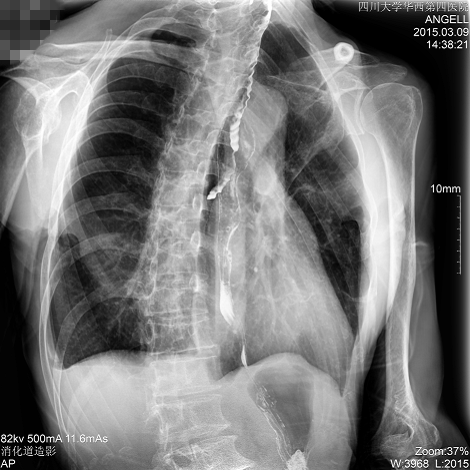

如下圖所示:該患者因吞咽時(shí)感到很難受,進(jìn)食時(shí)也經(jīng)常咳嗽故就醫(yī)診斷。華西醫(yī)院醫(yī)生使用動(dòng)態(tài)DR為病人進(jìn)行消化道造影診斷,要求他吞鋇后發(fā)現(xiàn),食道各段通過(guò)順利,形態(tài)規(guī)則,雙側(cè)梨狀窩不對(duì)稱左側(cè)稍淺,多次吞咽動(dòng)作后,仍見鋇劑滯留,并見鋇劑進(jìn)入氣管,屬于會(huì)厭征陽(yáng)性。會(huì)厭功能紊亂,鋇劑進(jìn)入了氣管。

圖為斜位:通過(guò)動(dòng)態(tài)影像可以清楚看到鋇劑進(jìn)入了支氣管道